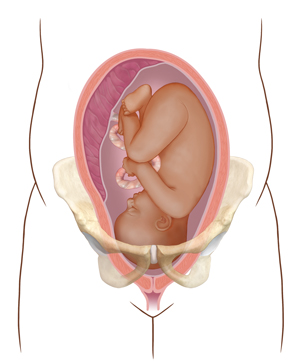

The wrong position. The baby is facing feet or buttocks first (breech position). Or the baby is lying sideways across the pelvis.

|

| Wrong position |